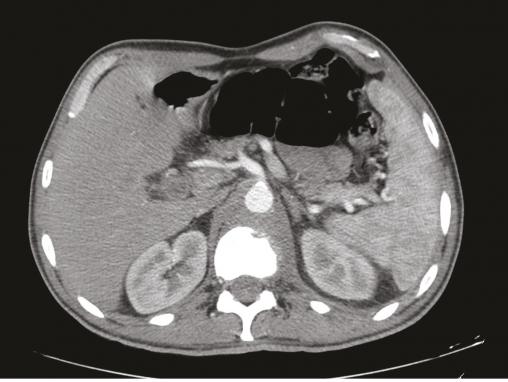

Figure 1. TDM, coupe axiale, fibrose rétropéritonéale refoulant l’aorte en avant avec lyse de L1.

Cet homme de 53 ans consultait pour une douleur de la charnière dorsolombaire à irradiation antérieure, mal calmée par les antalgiques, avec un amaigrissement sans fièvre. L’examen clinique trouvait une raideur rachidienne et le bilan biologique montrait un syndrome inflammatoire. La tomodensitométrie (TDM) abdominale révélait une fibrose rétropéritonéale avec lyse de L1 (fig. 1 ). L’imagerie par résonance magnétique (IRM) montrait un aspect de fibrose rétropéritonéale secondaire, en hyposignal T1 et T2, se rehaussant après injection du gadolinium avec lyse de L1 (fig. 2 ). La tomographie par émission de positons au 18-fluorodésoxyglucose (TEP18-FDG) montrait un hypermétabolisme intense de L1 dont la biopsie scannoguidée révélait un granulome épithélio-giganto-cellulaire cadrant avec une tuberculose (fig. 3 ). Le patient était efficacement traité par les antibacillaires pendant 9 mois.